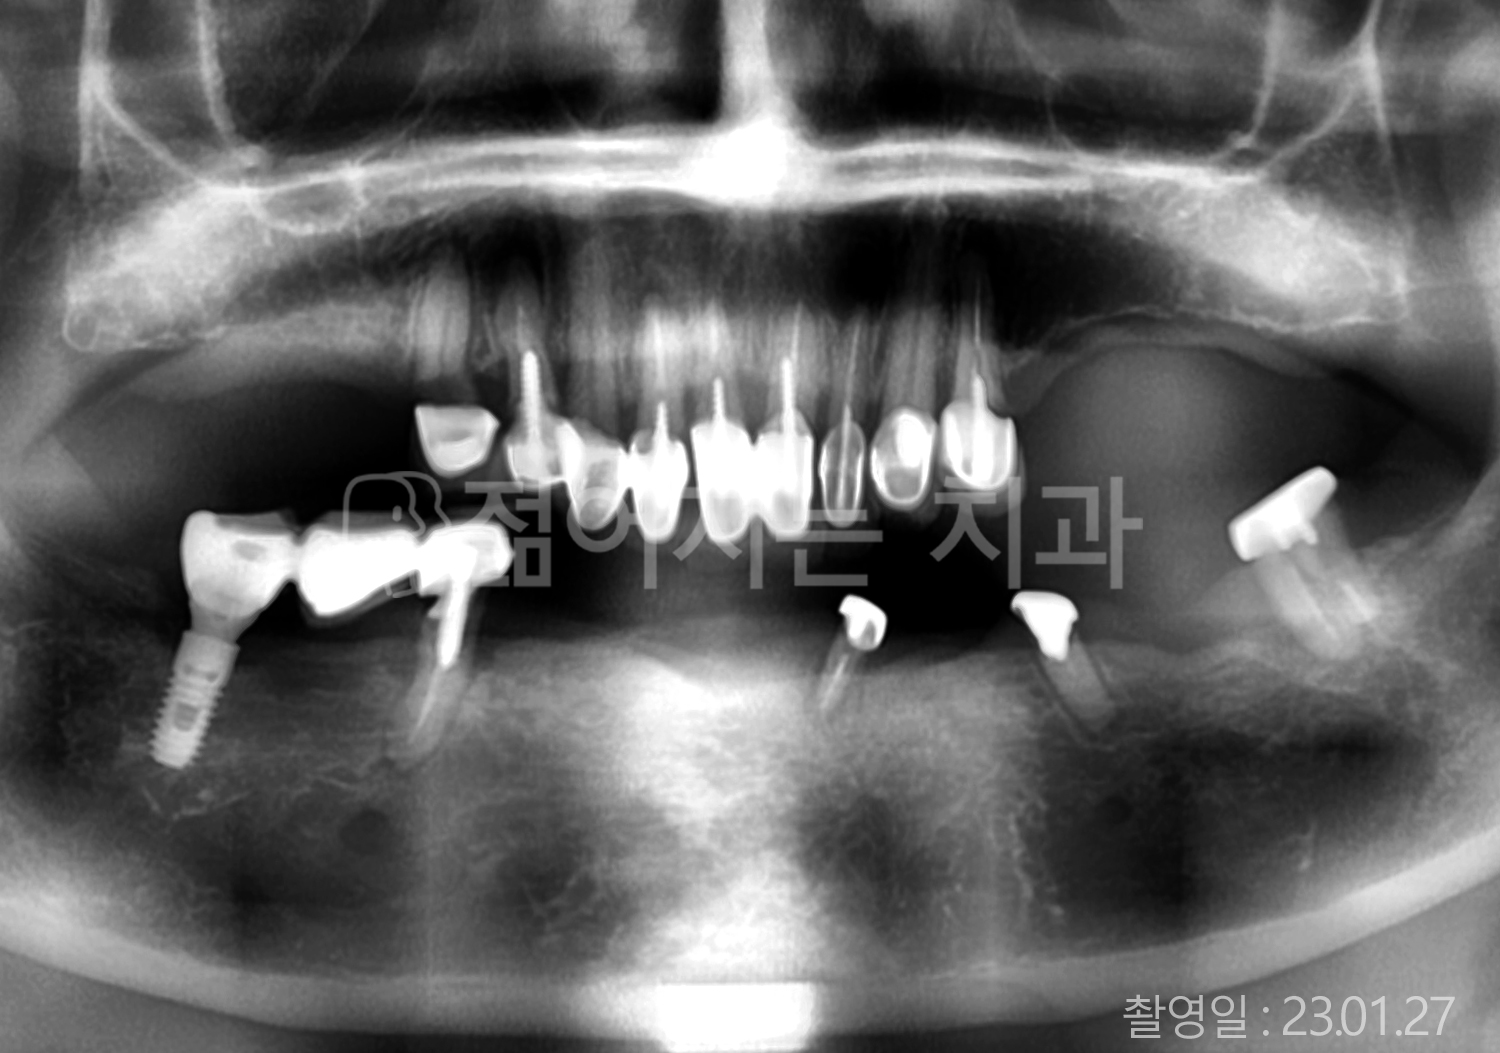

• 70대 고혈압, 고지혈증 전체치아 10개 이상 임플란트

• 60대 당뇨, 간염 전체치아 10개 이상 임플란트

• 80대 골다골증 전체치아 6개 이상 임플란트

• 70대 고혈압, 당뇨 전체치아 10개 이상 임플란트